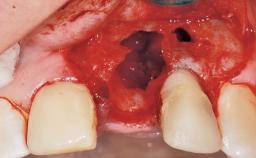

Immediate Placement of an Implant in a Maxillary Left Central Incisor Site

A 33-year-old female patient presented with an upper left central incisor that required extraction after a failed endodontic therapy. The tooth had been traumatized when the patient was a teenager and had undergone several endodontic treatments, including two apicectomy procedures. The patient was in good health and did not smoke. Clinical examination showed that the patient had a high lip line. In full smile, the gingival margins of the upper teeth were visible to the first molars. The gingival margins of central incisors 11 and 21 were only just showing. Examination of tooth 21 confirmed that the tooth was mobile and had hypererupted by 1 mm.

Placement Protocol Immediate implant placement

Socket Integrity Damage to one or more bone walls

Bone Volume Damage to one or more socket walls